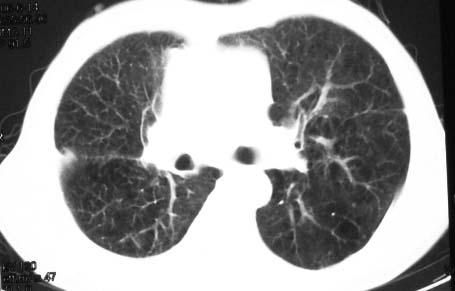

病史:男,64岁,咳血,咳痰,发热3天,wbc---1.2万

影象表现:右肺上叶大片状、网格状及索条致密影,蜂窝影,其内参杂斑点状小结节,密度不均匀,内见含气支气管像,纵隔内见肿大淋巴结.

抗炎10天后无好转出现胸水,考虑:肺结核合并间质纤维化

抗感染病变无明显改善,右上叶大片状增弥不均匀病灶,夹杂网状及支气管充气像,肺门纵隔淋巴结肿大,右侧胸腔积液。考虑1混合感染伴肺间质改变[警惕特殊感染,如真菌]。2细支气管肺泡癌。建议结合临床及进一步检查[如痰,胸水脱落细胞检查及支气管镜检灌洗或穿刺活检

影象表现:右肺上叶大片状、网格状及索条致密影,蜂窝影,其内参杂斑点状小结节,密度不均匀,内见枯枝样含气支气管像,纵隔内见肿大淋巴结.胸膜广泛增厚,前胸壁似受累.少量胸腔积液.纵隔内淋巴结的直径>1.5cm.右侧胸廓体积缩小.考虑:1 肺结核合并间质纤维化 2 细支气管肺泡癌

右肺上叶大片状、网格状及索条致密影,蜂窝影,其内参杂斑点状小结节,密度不均匀,内见枯枝样含气支气管像,纵隔内见肿大淋巴结.胸膜广泛增厚,前胸壁受累增厚.少量胸腔积液.纵隔内淋巴结的直径>1.5cm.右侧胸廓体积缩小.考虑: 细支气管肺泡癌并肺内癌性淋巴管炎。